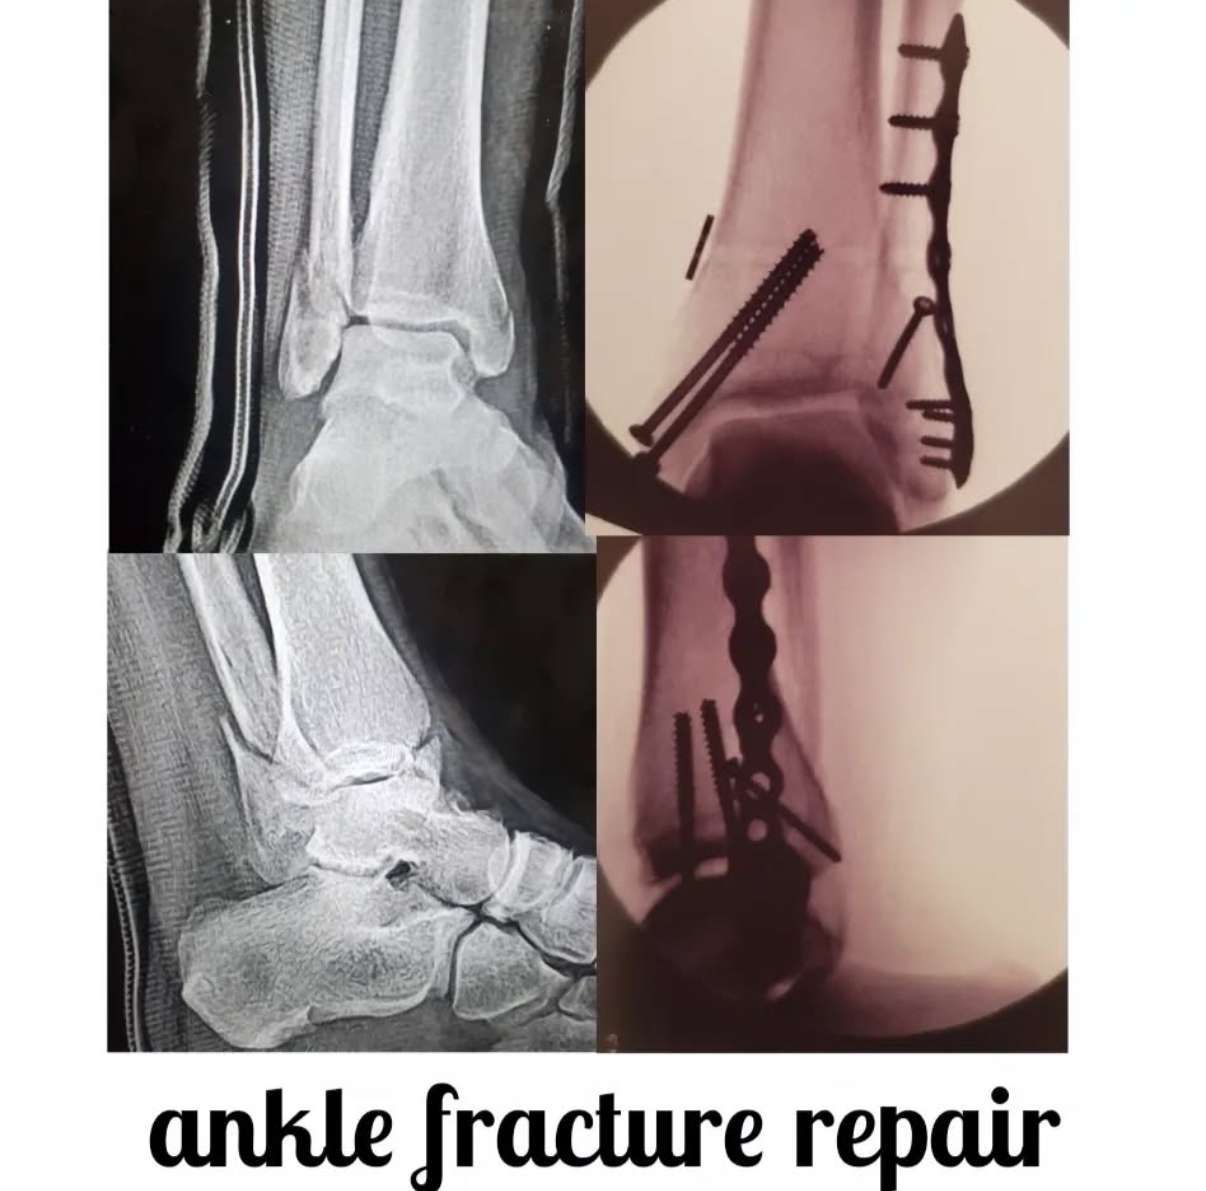

Ankle fracture repair

AF1

AF2